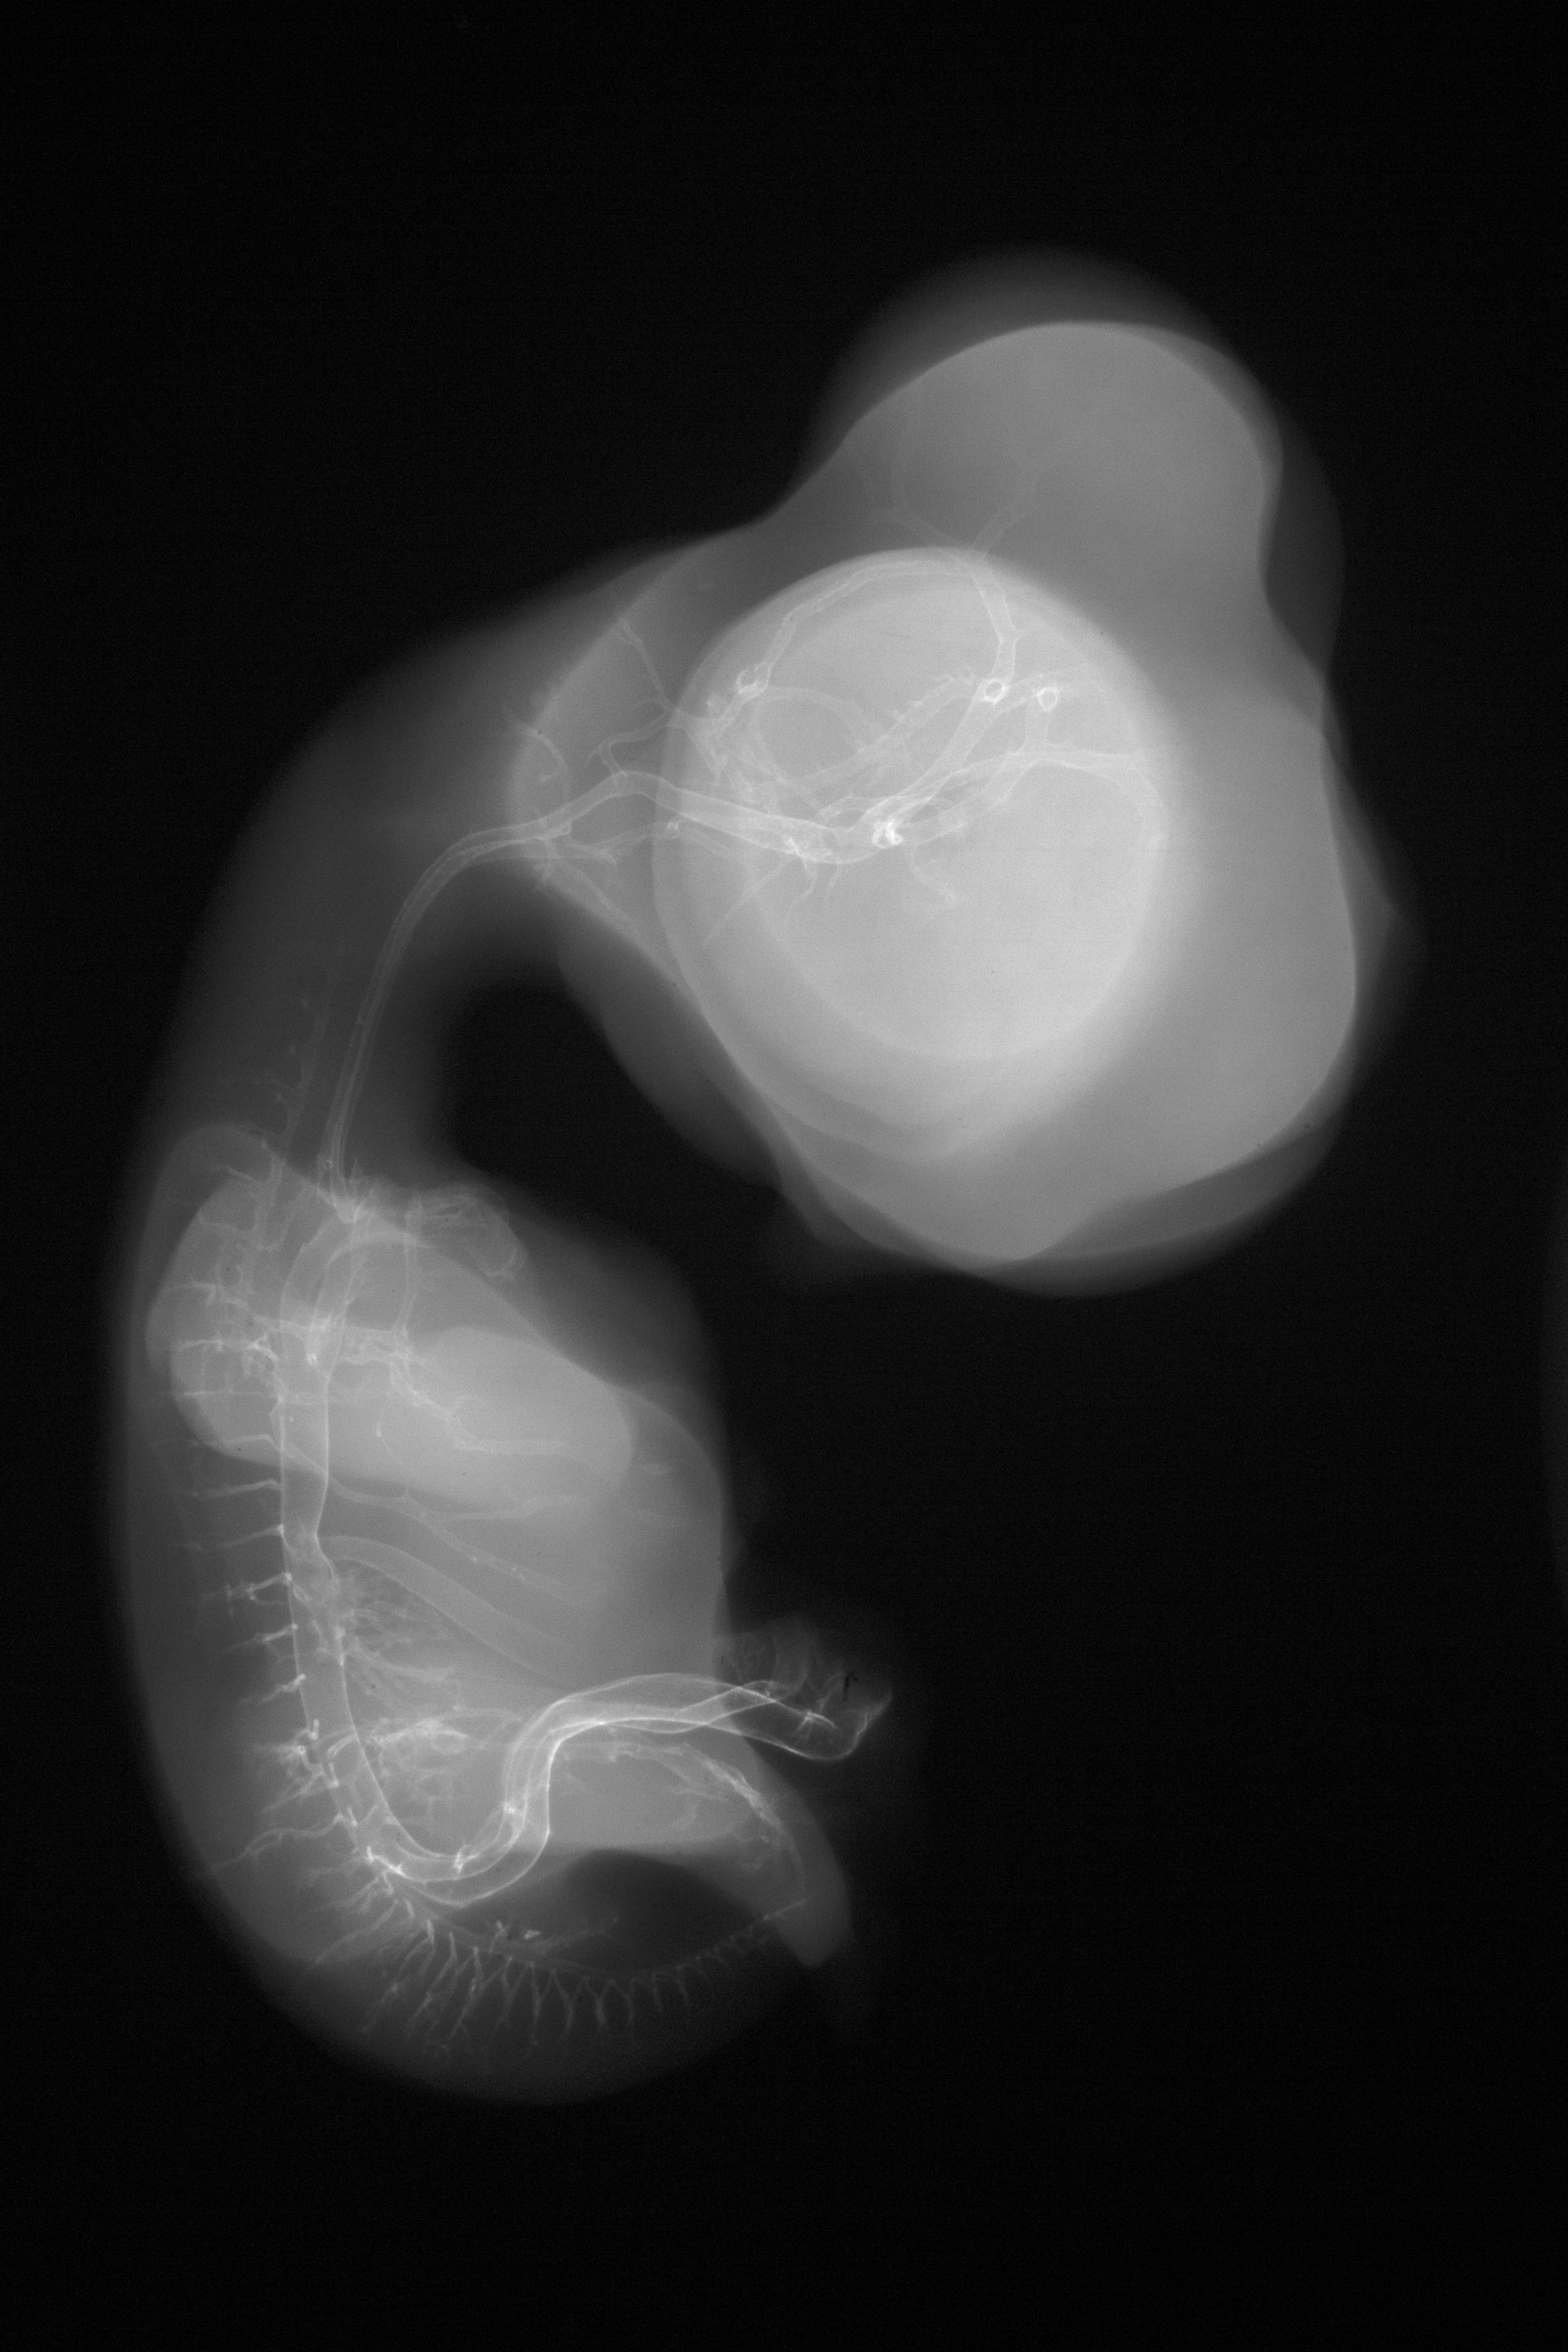

Chick Embryo Microangiography

Hamburger-Hamilton (HH) Stage 30 (approx. 6.5 days)

Stereo X-Ray Micrographs